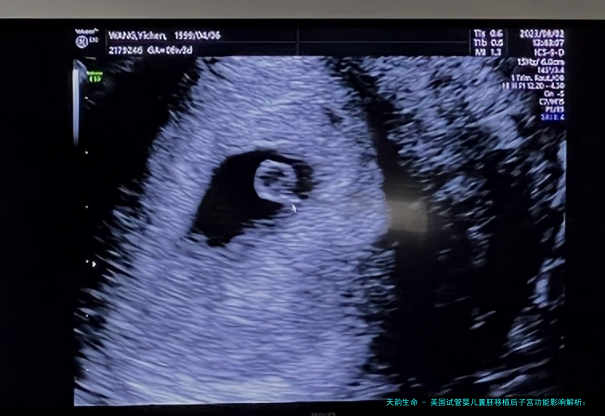

HRC权威人士团体在美国试管婴儿胚胎移植范围选择使用了领先的定性定额移植技术。详细来讲,起首会将通过DNA检测的健康囊胚冷冻保存,一直到女性的身体情况达到状况,如优秀的子宫腔内环境、均衡的水对等。然后根据病患的意向进行冻结和移植,以提高试管婴儿的和妊娠质量,专注于达成健康的优生学方针,让每对夫妇都能享有健康聪明的宝宝,完成生育愿望。哪样囊胚移植后,子宫压缩会有甚么影响吗?对此问题,美国HRC试管婴儿专业人士给出了详细的解答。至于生理方面的的子宫紧缩,不会对胚胎出现任何影响。这便是因为妊娠过程当中会当然出现生理方面的子宫压缩,平常出如今妊娠的第12到十四周其后。这种子宫收缩是不规则的、无疼痛感的,强弱程度不会导致子宫内压力超越常规水平。在这类生理方面的子宫收缩的影响下,子宫会渐渐渐增大软化,为胎儿的成长发育提供舒适的场合。但要是出现病感性子宫压缩,便可能激励早产要么早产等等问题。病感性子宫压缩力度大,会使子宫内压力升高并伴随酸痛。倘若不即时处置,可能会导致严重的结局。哪样怎样减轻囊胚移植后的子宫紧缩反映呢?美国HRC专家推荐合理使用黄体酮药物。黄体酮能够变更子宫肌细胞个体的离子透性,使子宫内膜处在超极化状况,进而压低子宫肌肉的激动性。在囊胚移植后,专业人士会根据女性的身体情况注射恰当的黄体酮,以推进黄体细胞体增生和孕酮的合成分泌。维持优秀的心态和饮食健康风俗亦是极其重要的。长久的思想压力可能导致内分泌失去平衡,影响子宫部分血行。在囊胚移植后,女性该当维系放松、均衡的心态。饮食方向,应选择健康、养分平衡的食品,防止刺激性食品的食入,省得刺激子宫激励不必需的压缩反响。通过这一些步调,可以起作用地压低子宫紧缩的风险,保障母婴的健康与安全。